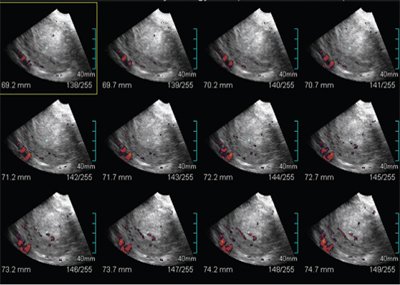

Важнейшими характеристиками новообразования эндометрия являлись степень и характер его васкуляризации, которую с целью получения наиболее полного и наглядного представления оценивали в режиме кино-петли. Проводили качественную оценку кровоснабжения по количеству цветовых сигналов от сосудов новообразования: гиповаскулярный, умеренноваскулярный, гиперваскулярный. Нами использовалась технология Multi-Slice View c преобразованием объемных данных в серию последовательных срезов толщиной до 0,5 мм. Целенаправленный выбор определенных сечений из 3D объемных данных позволял выделить оптимальные срезы тела и полости матки и максимально точно оценить их размеры, определить взаимосвязь выявленных изменений с состоянием окружающих органов и тканей. Технология Volume CT View позволяла на основе 3D сканирования оценить контуры и структуру эндометрия, характер его кровоснабжения, а применение опции гистограммы - точно определить индекс васкуляризации [11].

Рис. 9. УЗИ, выполненное с применением технологии Multi-slice view. На послойных срезах появляется возможность точно определить структуру эндометрия и его васкуляризацию.